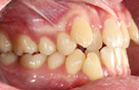

齒顎矯正即是指藉由固定或活動的矯正裝置,將口腔內舉凡牙齒排列不正,如齒列排列不整、牙齒間隙過大、犬齒外突等、骨關係不協調,如戽斗、暴牙、開咬、深咬、中線偏移、嘴巴歪斜等,透過牙齒矯正達到下列之治療目的: